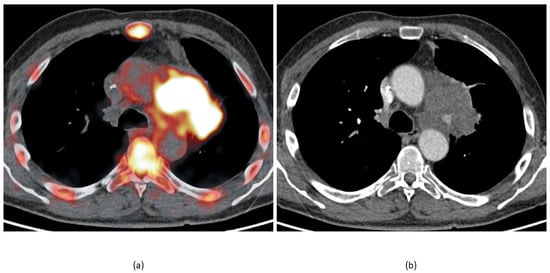

- Koa, B.; Borja, A.J.; Yellanki, D.; Rojulpote, C.; Tran, J.; Zhang, V.; Werner, T.J.; Alavi, A.; Revheim, M.-E. 18F-FDG-PET/CT in the assessment of atherosclerosis in lung cancer. Am. J. Nucl. Med. Mol. Imaging 2021, 11, 1–9. [Google Scholar]

- Rominger, A.; Saam, T.; Wolpers, S.; Cyran, C.C.; Schmidt, M.; Foerster, S.; Nikolaou, K.; Reiser, M.F.; Bartenstein, P.; Hacker, M. 18F-FDG PET/CT Identifies Patients at Risk for Future Vascular Events in an Otherwise Asymptomatic Cohort with Neoplastic Disease. J. Nucl. Med. 2009, 50, 1611–1620. [Google Scholar] [CrossRef] [PubMed]